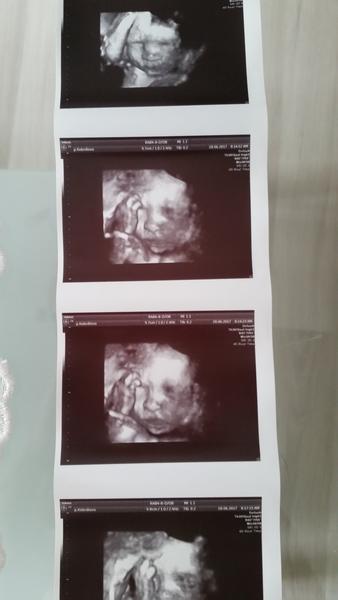

@pulguita tak je to za nami maly si daval rucicku pres oblicej ale neco se povedlo zachytit😉tak chlapecka nam nikdo neodpare je to na tuty😀vyfotila mu i pindika😀jdu pripravovat obed prijede ten pritele kolega a zacnou delat🙂to jsi dobra ze si vybehla a 5km za pul hodiny????tak to bych nedala ale ja az porodim tak chci taky zacit behat😀krasnou stredu

@petrysek181 To je kraaasna fotecka,aspon ze nee vsechny miminka nejsou jako to nase,co se proste neukaze a neukaze😂

@petrysek181 No ten je nádherný😍 Hezky jde vidět. Co na to přítel? Byl na měkko? 🙂

Krásnou středu a zarámuj si tu fotečku, opravdu se povedla🙂